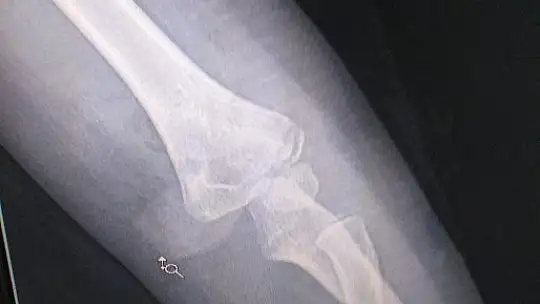

Foça Mahallesi Çalış Mevkii’nde anne ve babası ile babaannesinin bulunduğu Melisa 2 Sitesi’ne giden 3,5 yaşındaki İdil Gençay sahipli bir köpeğin saldırısına uğradı. Akita cinsi köpek tarafından kolundan ısırılarak silkelenen ve yere düşen İdil kanlar içinde kaldı. Dirsek kemiği kırılan; kasları ve tendonu kopma noktasına gelen İdil, köpekten kurtarılıp hastaneye yetiştirildi ve ameliyata alındı. Fethiye Lokman Hekim Esnaf Hastanesi’ne kaldırılan İdil,  Plastik Cerrah Op. Dr. Barış Yiğit tarafından mikro cerrahi yöntemi ile ameliyat edildi. Küçük kızın damarının ve ana sinirlerin şans eseri kopmadığı, yüzeysel bir sinirin zarar gördüğü ve dikildiği ancak  6 hafta boyunca kolunun alçıda kalması ve sonrasında uzun bir sure fizik tedavi görmesi gerekeceği belirtildi.

İdil Gençay’ın babası Avukat Meriç Gençay yaptığı açıklamada, “Kızımı ve oğlumu 28 Nisan 2021 akşamı saat 18.00 civarında evimize yaklaşık 300 metre uzaklıkta olan babaannesinin ve dedesinin oturduğu Melisa 2 Sitesi’ne götürdüm. Bu site geniş bir yeşil alanı olan ve çocuklarımın da arkadaşlarıyla bahçede oynadığı yaklaşık 100-150 daireden oluşan büyük bir sitedir. Olay zamanında ben giriş kat balkonunda otururken çocuklar 30-40 metre ileride gözümüzün önünde, bahçede oynuyorlardı. Saat 18.40’ta bir çocuk çığlığı duydum, arkasından diğer çocukların bağırışları başladı. Hemen yerimden kalkarak koşarak sesin geldiği yöne koştum. Kızım yerde kolu kan içinde yatmaktaydı, üzerinde uzun kollu bir tişört vardı ve sol kolu tamamen kan olmuştu. Yanında saldıran köpek durmaktaydı. Hemen kızımı kucağıma aldım ve hastaneye götürdüm. Saldırı anını bizzat görmedim. Saldırı neticesinde kızım İdil’in dirseğini iç kısmında bulunan tendon ve kaslar kopmuş, dirsek kemiği kırılmıştır. Aynı akşam plastik cerrah tarafından Esnaf Hastanesi’nde ameliyat olmuştur. Kolunun 6 hafta alçıda kalması gerektiği ve sonrasında da fizik tedavi görmesi gerektiği tarafımıza söylenmiştir. Saldıran köpek Amerikan Akita cinsi, kurt köpeği boyutlarında büyük bir köpektir. Bu köpek, bekçi köpeği olarak kullanılan, avcılık ve dövüşçülük özellikleri baskın,  Amerika CDC tarafından tehlikeli köpek listesine alınmış ve Amerika'nın birçok eyaletinde beslenmesi yasaklanmış bir köpektir. Kayda geçmiş dört adet insan öldürme ve bir çok saldırı vakası vardır. Sahibi dışındaki tüm insanları ve diğer hayvanlara karşı saldırgan ve eğitimi zor bir köpektir. Bu nedenle, toplu konut alanlarında veya müstakil olmayan yerlerde beslenmesi tehlikelidir. Sahibi bu köpeği site içerinde, giriş kattaki evinin balkonunda, bir bahçe çitinin ardında beslemektedir. Köpek evin önünden geçen herkese saldırı pozisyonuna geçerek havlamaktadır. Bu yüzden zaten korktuğumuz ve uzak durduğumuz bir köpektir. Köpek sahibi M.A’dan şikayetçi olduk” diye konuştu.